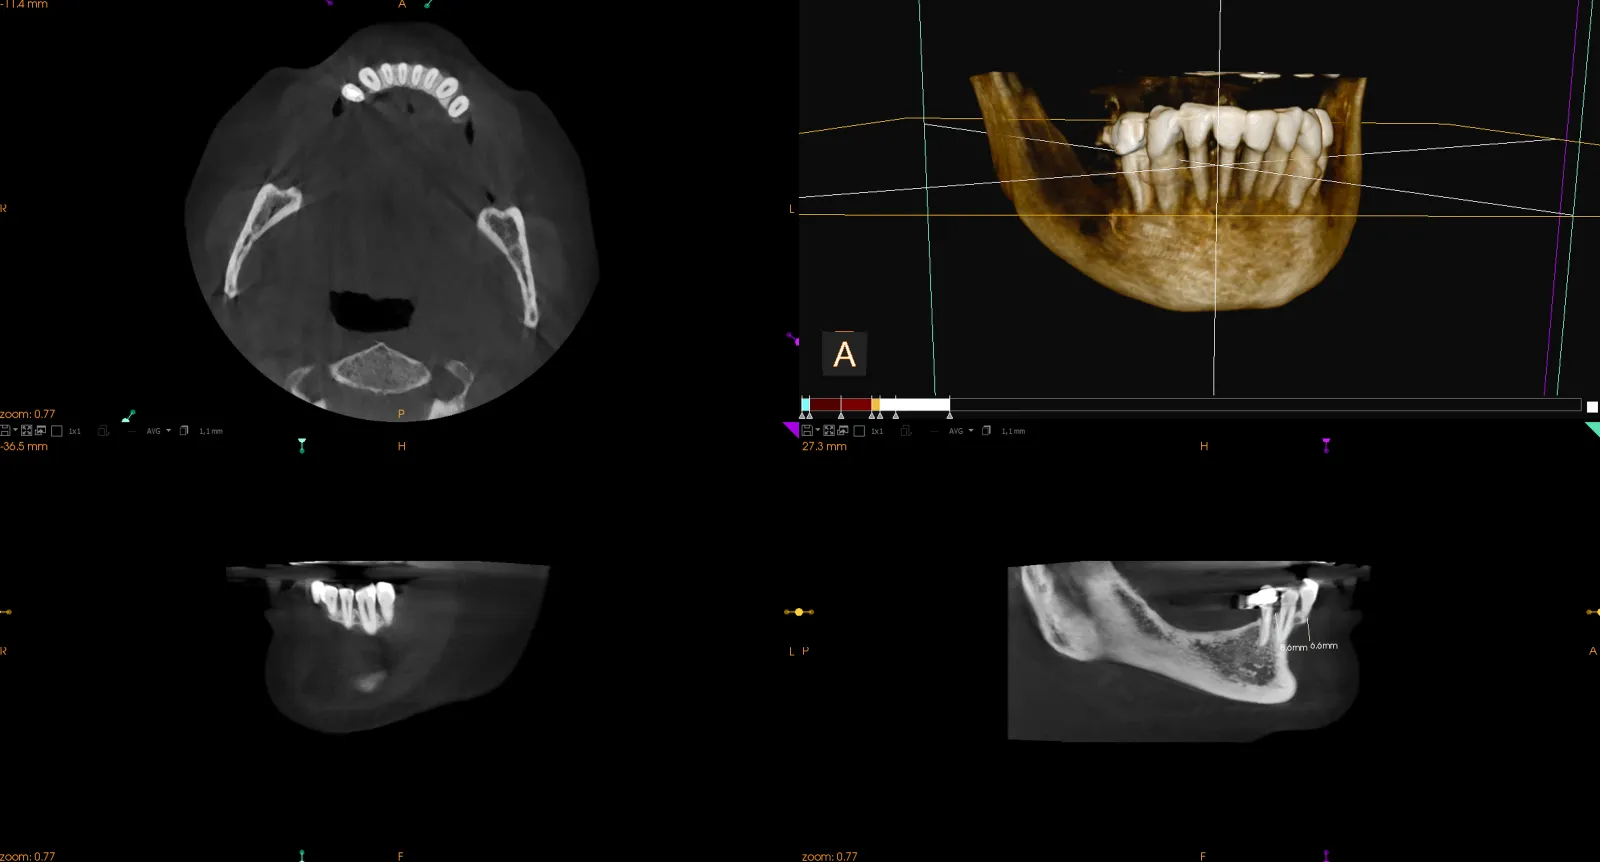

Zdjęcie 3D najczęściej stosowane jest w leczeniu implantologicznym. Pozwala na określenie wysokości i szerokości wyrostka zębodołowego, są to niezbędne wartości, pozwalające zaplanować umieszczenie samego implantu. Jednak to nie jedyne zastosowanie RTG 3D zębów. W leczeniu endodontycznym umożliwia odnalezienie dodatkowych kanałów, wszelkiego rodzaju złamań i ewentualnych pęknięć, a także pozwala wykluczyć złamane narzędzia endodontyczne, znajdujące się w zębie. Z tak precyzyjnej metody badania korzystają również periodontolodzy i chirurdzy szczękowi.

Wirtualna rekonstrukcja umożliwia wcześniejsze zaplanowanie leczenia, któremu finalnie poddaje się pacjenta. Analogiczny sposób prowadzenia zabiegu pozwala uniknąć wielu błędów i niespodzianek, jakie może napotkać dentysta w trakcie pracy z pacjentem. Co bardziej istotne — każdą strukturę można ujrzeć bez zniekształceń i pod dowolnym kątem.